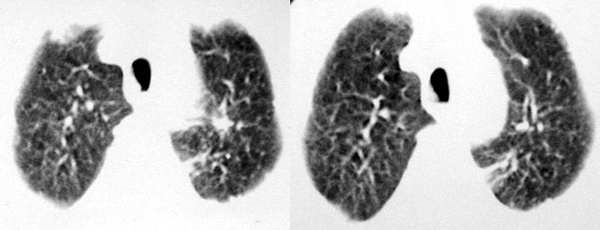

以下是引用sdqzwyx在2005-11-7 19:59:00的发言:[br]双肺弥漫大小不等的粟粒状结节影;肺纹理走行失去自然,粗细不均,边缘不规则,小叶间隔增厚;左上肺示不规则形致密影,从斑块边缘向周围伸出长短不一的致密索条影,临近的血管、支气管和叶间胸膜等结构受牵拉移位;左下肺示不规则团块状影,其内示空洞,洞内壁尚光整,左侧胸腔积液。右肺下叶背段亦示部分病灶融合。双肺可见局限性肺气肿。[br]诊断:结合病史符合三期矽肺表现(少数矽肺纤维斑块内可以形成空洞,一般认为是斑块中央感染引起坏死所致)但尘肺病人易合并肺结核,诊断可为三期+tb。所以此病人应进一步检查是否合并结核。